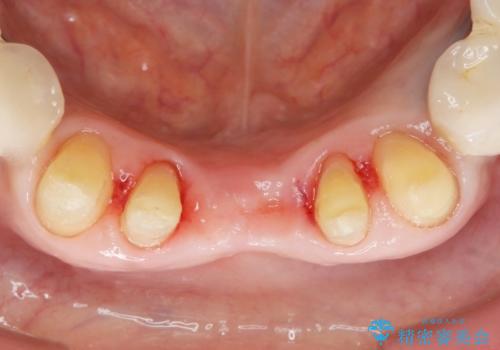

抜歯後歯肉の治癒を十分に待ったのち、ブリッジによる補綴治療を行いました。

歯周病が重度であったため抜歯後の歯肉の陥凹が大きく、GBRや歯肉移植による歯周組織の再建をおすすめしましたが、ご希望されませんでした。

上の前歯の再根管治療もおすすめしましたが、必要性を感じないとのことで土台のやりかえだけをご希望されました。